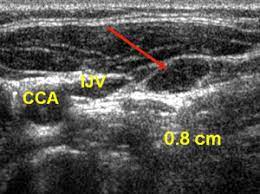

Spread of thyroid cancer to the lymph nodes in the neck is common and increases the risk of cancer recurrence. I had an ultrasound done in 2012 but the report for this scan never reached my previous doctor's practice and so nothing was. Ultrasound uses sound waves to create images of the body on a computer monitor. 8.4, 8.5, 8.6, 8.7, and 8.8). The first lymph node cancer cells spread to is known as the sentinel node.

The lymph nodes in the neck are often the first place cancer cells spread to outside the primary site. If cancer is found in a lymph node, you may need a neck dissection or other additional treatment. An ultrasound does not have the resolution to see cancer cells. Ultrasounds have many limitations an ultrasound is not good enough for many aspects of cancer. Fna might also be used in patients whose cancer has been treated by surgery and/or radiation therapy , to help find out if a neck mass in the treated area is scar tissue or if it's a return (recurrence) of the cancer. Ultrasound uses sound waves to create images of the body on a computer monitor. In some cases, your ultrasound may show images of nodules that may or may not be cancerous or contain microcalcifications, which is often associated with cancer. Ultrasound imaging is a noninvasive medical test that helps physicians diagnose and treat medical conditions. Additionally, how do they test for thyroid cancer? Lymph nodes are part of the lymphatic system, which helps to protect us from infection and disease. Ultrasound guidance is used to perform thyroid biopsies and improves the diagnostic accuracy of fine needle biopsy. Carotid ultrasound tests for blocked or narrowed carotid arteries, which can increase the. But according to one study, cancer.

Colon Cancer Ultrasound Radiology Case Radiopaedia Org from prod-images-static.radiopaedia.org To see whether the cancer has spread, some or all of the lymph nodes are removed and checked for cancerous cells. We prospectively studied 19 patients referred to the institut gustave. It can be used with a fine needle aspiration test or core biopsy test to accurately direct the tip of the needle into the lump. If this lump is of concern then a biopsy would be the next step. They deliver blood from your heart to your brain. Head and neck cancers include cancers in: However, an ultrasound can tell if a lymph node has an abnormal architecture possibly because it is infiltrated by tumor. Sonography, when performed by an experienced examiner, can be used for evaluation of many pathologies in the head and neck area.

An ultrasound of the thyroid produces pictures of the thyroid gland and the adjacent structures in the neck. The scan is painless and only takes a few minutes. It can detect abnormal tissues, growths, and cysts and give a suspicion of cancer based on how those images look. Confirming that a lump in the neck is developing from the thyroid or connected tissue. Doctors and pathologists do not use internal ultrasound scan frequently to detect lymphoma. Ultrasound guidance is used to perform thyroid biopsies and improves the diagnostic accuracy of fine needle biopsy. The first lymph node cancer cells spread to is known as the sentinel node. Ultrasounds can't show lung cancer or bone cancer. Some of the indications for thyroid or neck ultrasound are thyroid nodules, goiter, thyroid cancer and other neck masses. For neck or thyroid mass see ent. To see whether the cancer has spread, some or all of the lymph nodes are removed and checked for cancerous cells. Fna might also be used in patients whose cancer has been treated by surgery and/or radiation therapy , to help find out if a neck mass in the treated area is scar tissue or if it's a return (recurrence) of the cancer. The lymph nodes in the neck are often the first place cancer cells spread to outside the primary site.